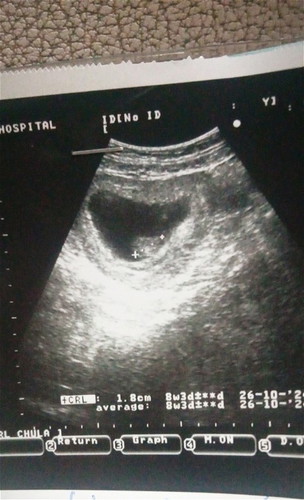

เลยไปตรวจที่ โรงบาลเพื่อให้ชัวร์ผลคือท้องหมอได้7สัปดาห์3วันนับจากประจำถ้านับมาจนถึงปัจจุบันตอนนี้จะอยุ่10สัปดาห์6วันเดือนมารอบสุดท้ายแต่อตอนนั้นที่ไปตรวจโรงบาลหมอทำการคล้ำดูท้องหมอบอกยังไม่มีถุงการตั้งครรค์เลยไม่ได้ซาวด์ดูถึงซาวด์ไปก็ไม่เจอเรยนัดวันที่8ก.คมาเพื่ออัลตราซาวด์ดูน้อง แต่เราดันปวดท้องมีมูกออกเป็นเลือดมื่อวันที่30ที่ผ่านเพราะติดเชื่อปัสวะหมอทำการซาวด์ได้8สัปดาห์2วันหัวใจเต้นปกติ #ปลหมอบอกแค่หัวใจเด็ดเต้นปกติไม่ได้บอกว่ากี่สัปดาห์แต่แม่หฝดูจากผลเองคะ อยากรู้ทำไมถึงผลซาวด์กับจากคำนวนของหมอที่คำนวนจากประจำเดือนไม่ตรงคะใครพอทราบช่วยอธิบายทีคะ ขอบคุณสำหรับคำตอบล่วงหน้าคะ